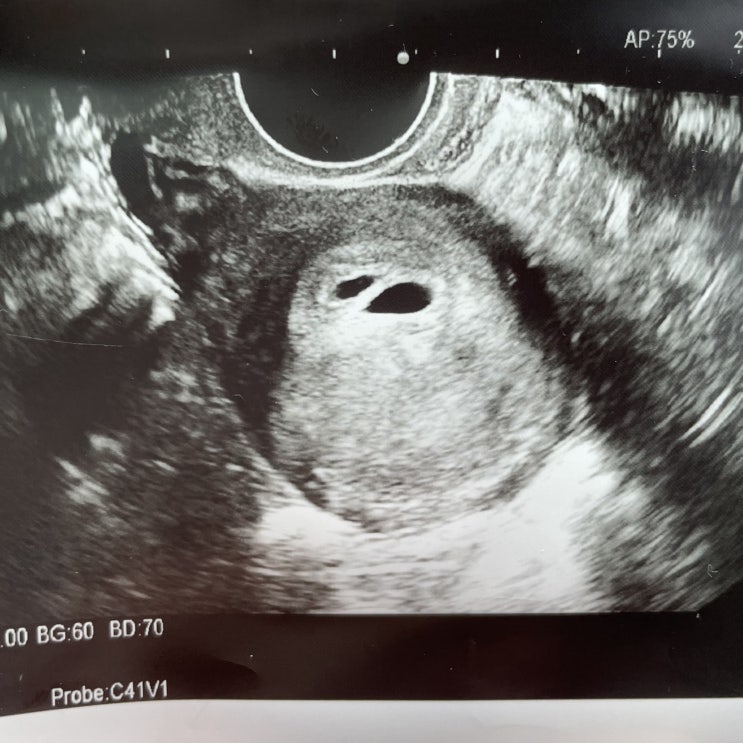

[임신일기] 시험관 임신 5주 - 7주 #쌍둥이소실 #베니싱트윈 #임신확인서 #보건소임산부등록 #서대문구보건소

2020년 11월 20일 (5주) 초음파를 보고 진료실로 갔습니다. 저번 초음파에서 피고임이냐고 했더니 아니라고...